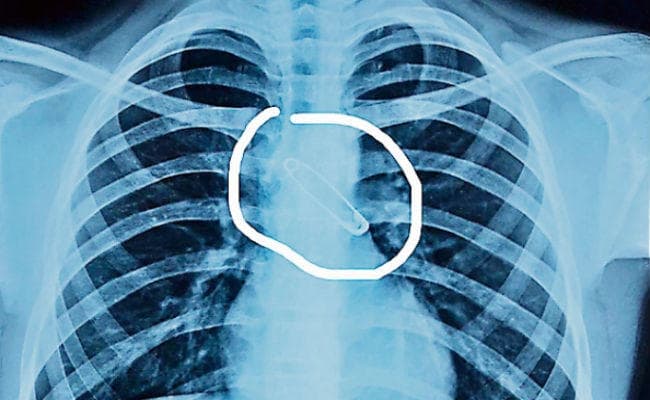

रांची : धनबाद निवासी 15 वर्षीय एक बच्चा टीवी पर कार्टून देखते वक्त अपने दांतों में सेफ्टी पिन दबाये हुए था. इसी बीच उसे खांसी आ गयी और बच्चे ने सेफ्टी पिन निगल लिया. बच्चे की जान सांसत में देख परिजन उसे डॉक्टर के पास ले गये, जहां एक्स-रे आदि जांच की गयी. पता चला कि सेफ्टी पिन बच्चे के फेफड़े के बायें भाग में जाकर फंसा हुआ है. चिकित्सक की सलाह पर परिजन उस बच्चे को लेकर राजधानी के लालपुर स्थित ऑर्किड मेडिकल सेंटर पहुंचे. यहां ब्रोंकोस्कोपी विधि से बच्चे की सांस की नली से सेफ्टी पिन को बाहर निकाला गया.

बच्चे का इलाज आॅर्किड मेडिकल सेंटर के पल्मोनरी मेडिसिन विभाग के डॉ निशीत कुमार और उनकी टीम ने किया. डॉ निशीत ने बताया कि सेफ्टी पिन की लंबाई पांच सेंटीमीटर थी. खास बात यह रही कि डॉक्टरों की टीम ने बच्चे को बेहोश किये बिना ही इस जटिल प्रक्रिया को पूरा किया. पिन निकालने के बाद कुछ आवश्यक दवा देकर बच्चे को घर भेज दिया गया. डॉ निशीथ कुमार ने बताया कि सांस की नली में फंसे पिन को अगर समय पर नहीं निकाला गया होता, तो बच्चे को सांस लेने में तकलीफ हो सकती थी, जो उसके लिए घातक हो सकता था.